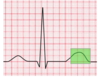

The airway pressure in this waveform clearly depicts dynamic hyperinflation, otherwise known as breath stacking. Patients with COPD have a longer expiratory time constant, and this means they require a longer period of time to exhale fully.

Of the answer choices provided, there are two options that reverse dynamic hyperinflation. By reducing the respiratory rate, the patient will spend more time over the course of a minute in E time. If PEEP becomes dangerously elevated, the definitive treatment for dynamic hyperinflation is to remove the patient from the ventilator.

Increasing inspiratory time is another way of saying reducing expiratory time, so this choice will actually make the patient’s condition worse. The inspiratory flow determines how fast the tidal volume is delivered to the patient. Increasing the inspiratory flow will deliver the preset tidal volume faster, and this does nothing to facilitate expiration.